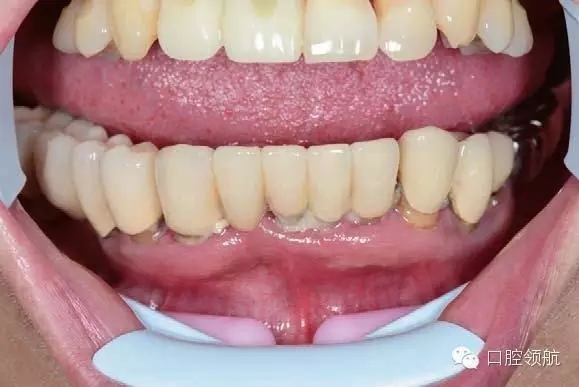

同時因為是即刻負重,為了減少不必要的風險,通常不制作遠中的游離端,該病例即刻負重過渡義齒修復到兩側(cè)的第二前磨牙,待永久修復時再增加兩側(cè)的第一磨牙。

圖6-15為術(shù)后4小時患者戴牙前的照片。由于女性患者通常附著齦較少、較薄,特別是下頜情況更為明顯,因此術(shù)后幾小時內(nèi)即可觀察到唇、舌側(cè)的黏膜淤血及腫脹。因此術(shù)后必須囑咐患者使用冰袋壓迫止血,必要時可以使用口外繃帶粘貼。

9.webp.jpg

圖6-15 戴牙前的牙合面照